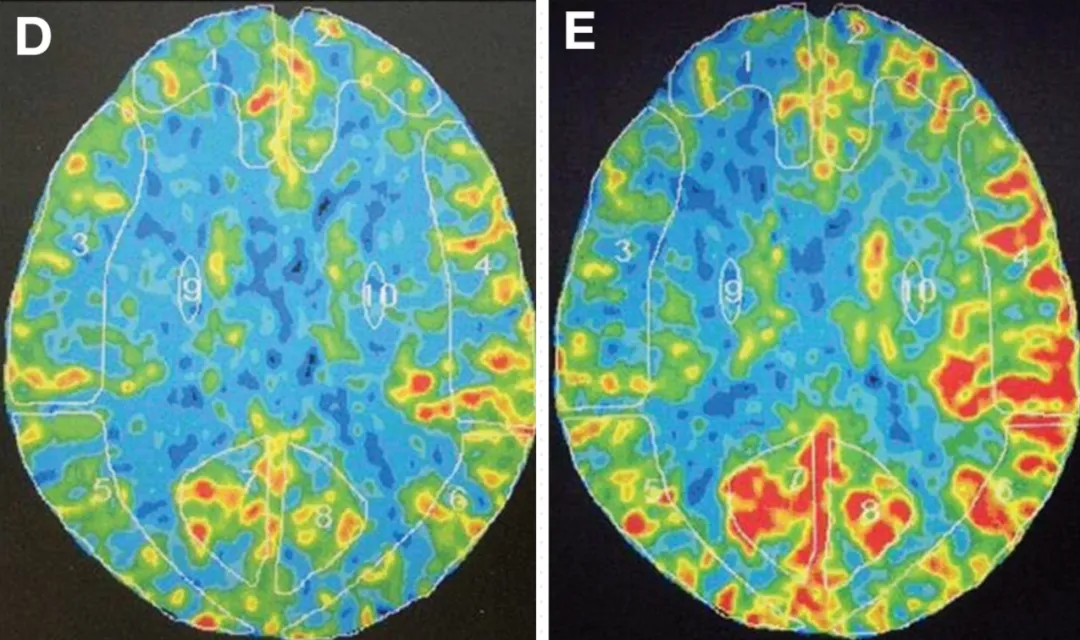

氙气CT脑血流检测结果显示,患者大脑前动脉区域不仅基础血流水平下降,对血管扩张药物(如乙酰唑胺)的反应性也显著减弱,提示该区域脑组织处于慢性缺血状态。这种血流动力学异常是导致患者出现肢体麻木症状的根本原因。